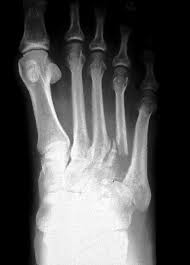

File Mast Cell Tumor Of The Toe Jpg Wikimedia Commons from upload.wikimedia.org The affected leg or joint develops pain that is often described as consistent and dull, like a persistent ache. For instance, lung cancer that spreads to the bone is made of lung cancer cells. Grade 1 (g1) means the cancer looks much like normal bone tissue. Ewing sarcoma also is more likely to be in kids and young. Grade 3 (g3) means the cancer looks very abnormal. In dogs, squamous cell carcinomas usually affect only one toe. It can look like a: Cancer hot spots can be seen in virtually any bone.

Sore that doesn't heal after seven to 10 days. The bone may look ragged, or it may appear to have a hole in it. Primary bone tumors can be either benign or malignant. Primary refers to cancer that starts in the bone versus spreading (metastasizing) into the bone from somewhere. Squamous cell carcinoma is the most common form of cancer on the skin of the feet. Grade 3 (g3) means the cancer looks very abnormal. Basal cell cancers may appear as pearly white bumps or patches that may ooze or crust and look like an open sore. Bone infections are most common in the leg, feet, hand, and arm bones. What bone metastasis looks like. Foot melanoma refers to cancer of the cells in the top layer of the skin on the foot. A tumor that has metastasized to bone is not made of bone cells. Skin cancer is the uncontrolled growth of abnormal skin cells, creating masses that destroy normal. It can also be like an intermittent.

Why Did Reagan Have A Toe Removed Dr Phil Zeltzman S Blog from www.drphilzeltzman.com It can spread to distant organs, such as the lungs. In fact, noncancerous bone tumors are much more common than cancerous ones. The scale used for grading bone cancer is from 1 to 3. A benign bone tumor of the foot will manifest as a lump, with or without pain, whereas bone cancer is most often accompanied by pain at the location of the tumor. A tumor that has metastasized to bone is not made of bone cells. People with bone sarcoma may experience the following symptoms or signs. It is important that all these symptoms are identified at an early stage so, to. Primary bone tumors are relatively rare after the fourth decade of life and less frequent as compared to secondary bone tumors.